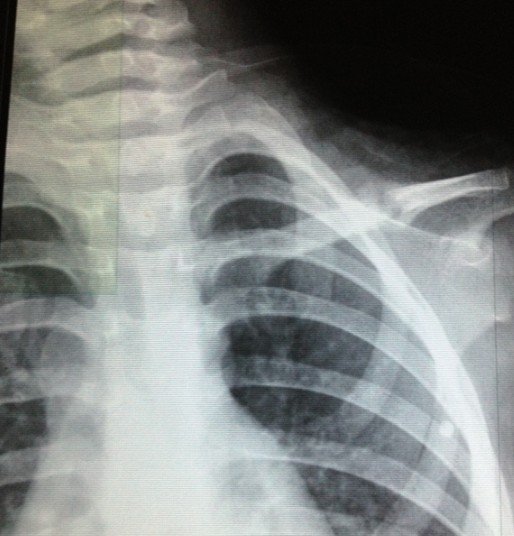

宝宝3岁半出车祸左锁骨骨折

患者信息:女 3岁 贵州 遵义 病情描述(发病时间、主要症状等):2012.10.7日发送车祸,X片确诊为左锁骨骨折。当天就打上八字绷带。想得到怎样的帮助:现在已经自行把八字绷带取下,请问这样做可以吗?因为孩子的腋下已经开始有轻微溃烂的症状(掉干壳壳)前段时间因为出车祸导致孩子的左锁骨骨折,去医院打了八字绷带,刚好一个月去医院复查,医生说已经开始长曾经治疗情况及是否有过敏、遗传病史:无

8字绷带笼殊还是没急着取下来,,才一个月,虽然骨痂生长饥训明显,,骨折断端对位对线也不错, 但仍不能绣殊崭太掉以轻心。再绑一个月估计才可去。 腋下涂点抗生素软膏就行。